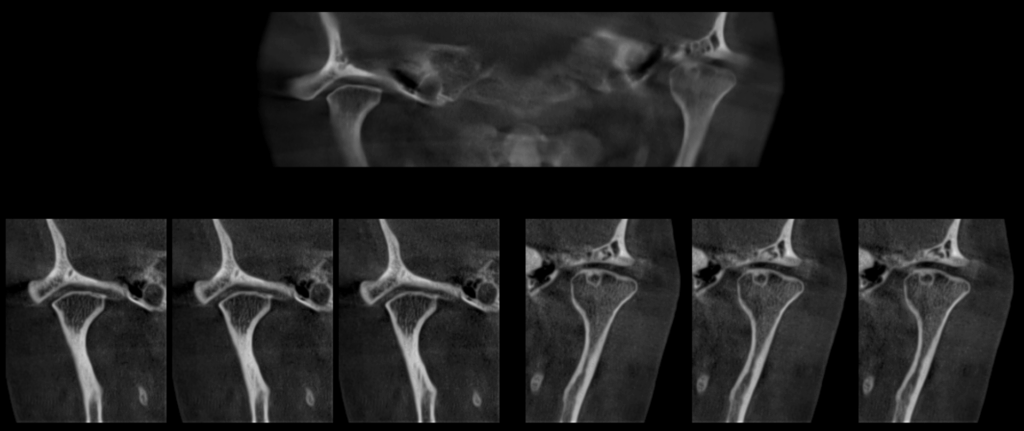

A la evaluación de la tomografía volumétrica (CBCT) de la ATM en boca cerrada, en los cortes axiales (Figura 2), coronales (Figura 3) y sagitales (Figura 4), se aprecia aplanamiento de la vertiente posterior del cóndilo mandibular del lado izquierdo con presencia de imagen hipodensa localizado próximo a la vertiente superior compatible con quiste subcondral, además se aprecia disminución de espacio articular posterior en ATM izquierda y disminución del espacio articular anterior en ATM derecha.

CORTES CORONALES

CORTES SAGITALES